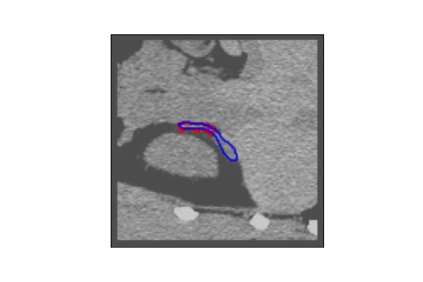

The human annotations are imperfect, especially when produced by junior practitioners. Multi-expert consensus is usually regarded as golden standard, while this annotation protocol is too expensive to implement in many real-world projects. In this study, we propose a method to refine human annotation, named Neural Annotation Refinement (NeAR). It is based on a learnable implicit function, which decodes a latent vector into represented shape. By integrating the appearance as an input of implicit functions, the appearance-aware NeAR fixes the annotation artefacts. Our method is demonstrated on the application of adrenal gland analysis. We first show that the NeAR can repair distorted golden standards on a public adrenal gland segmentation dataset. Besides, we develop a new Adrenal gLand ANalysis (ALAN) dataset with the proposed NeAR, where each case consists of a 3D shape of adrenal gland and its diagnosis label (normal vs. abnormal) assigned by experts. We show that models trained on the shapes repaired by the NeAR can diagnose adrenal glands better than the original ones. The ALAN dataset will be open-source, with 1,594 shapes for adrenal gland diagnosis, which serves as a new benchmark for medical shape analysis. Code and dataset are available at https://github.com/M3DV/NeAR.